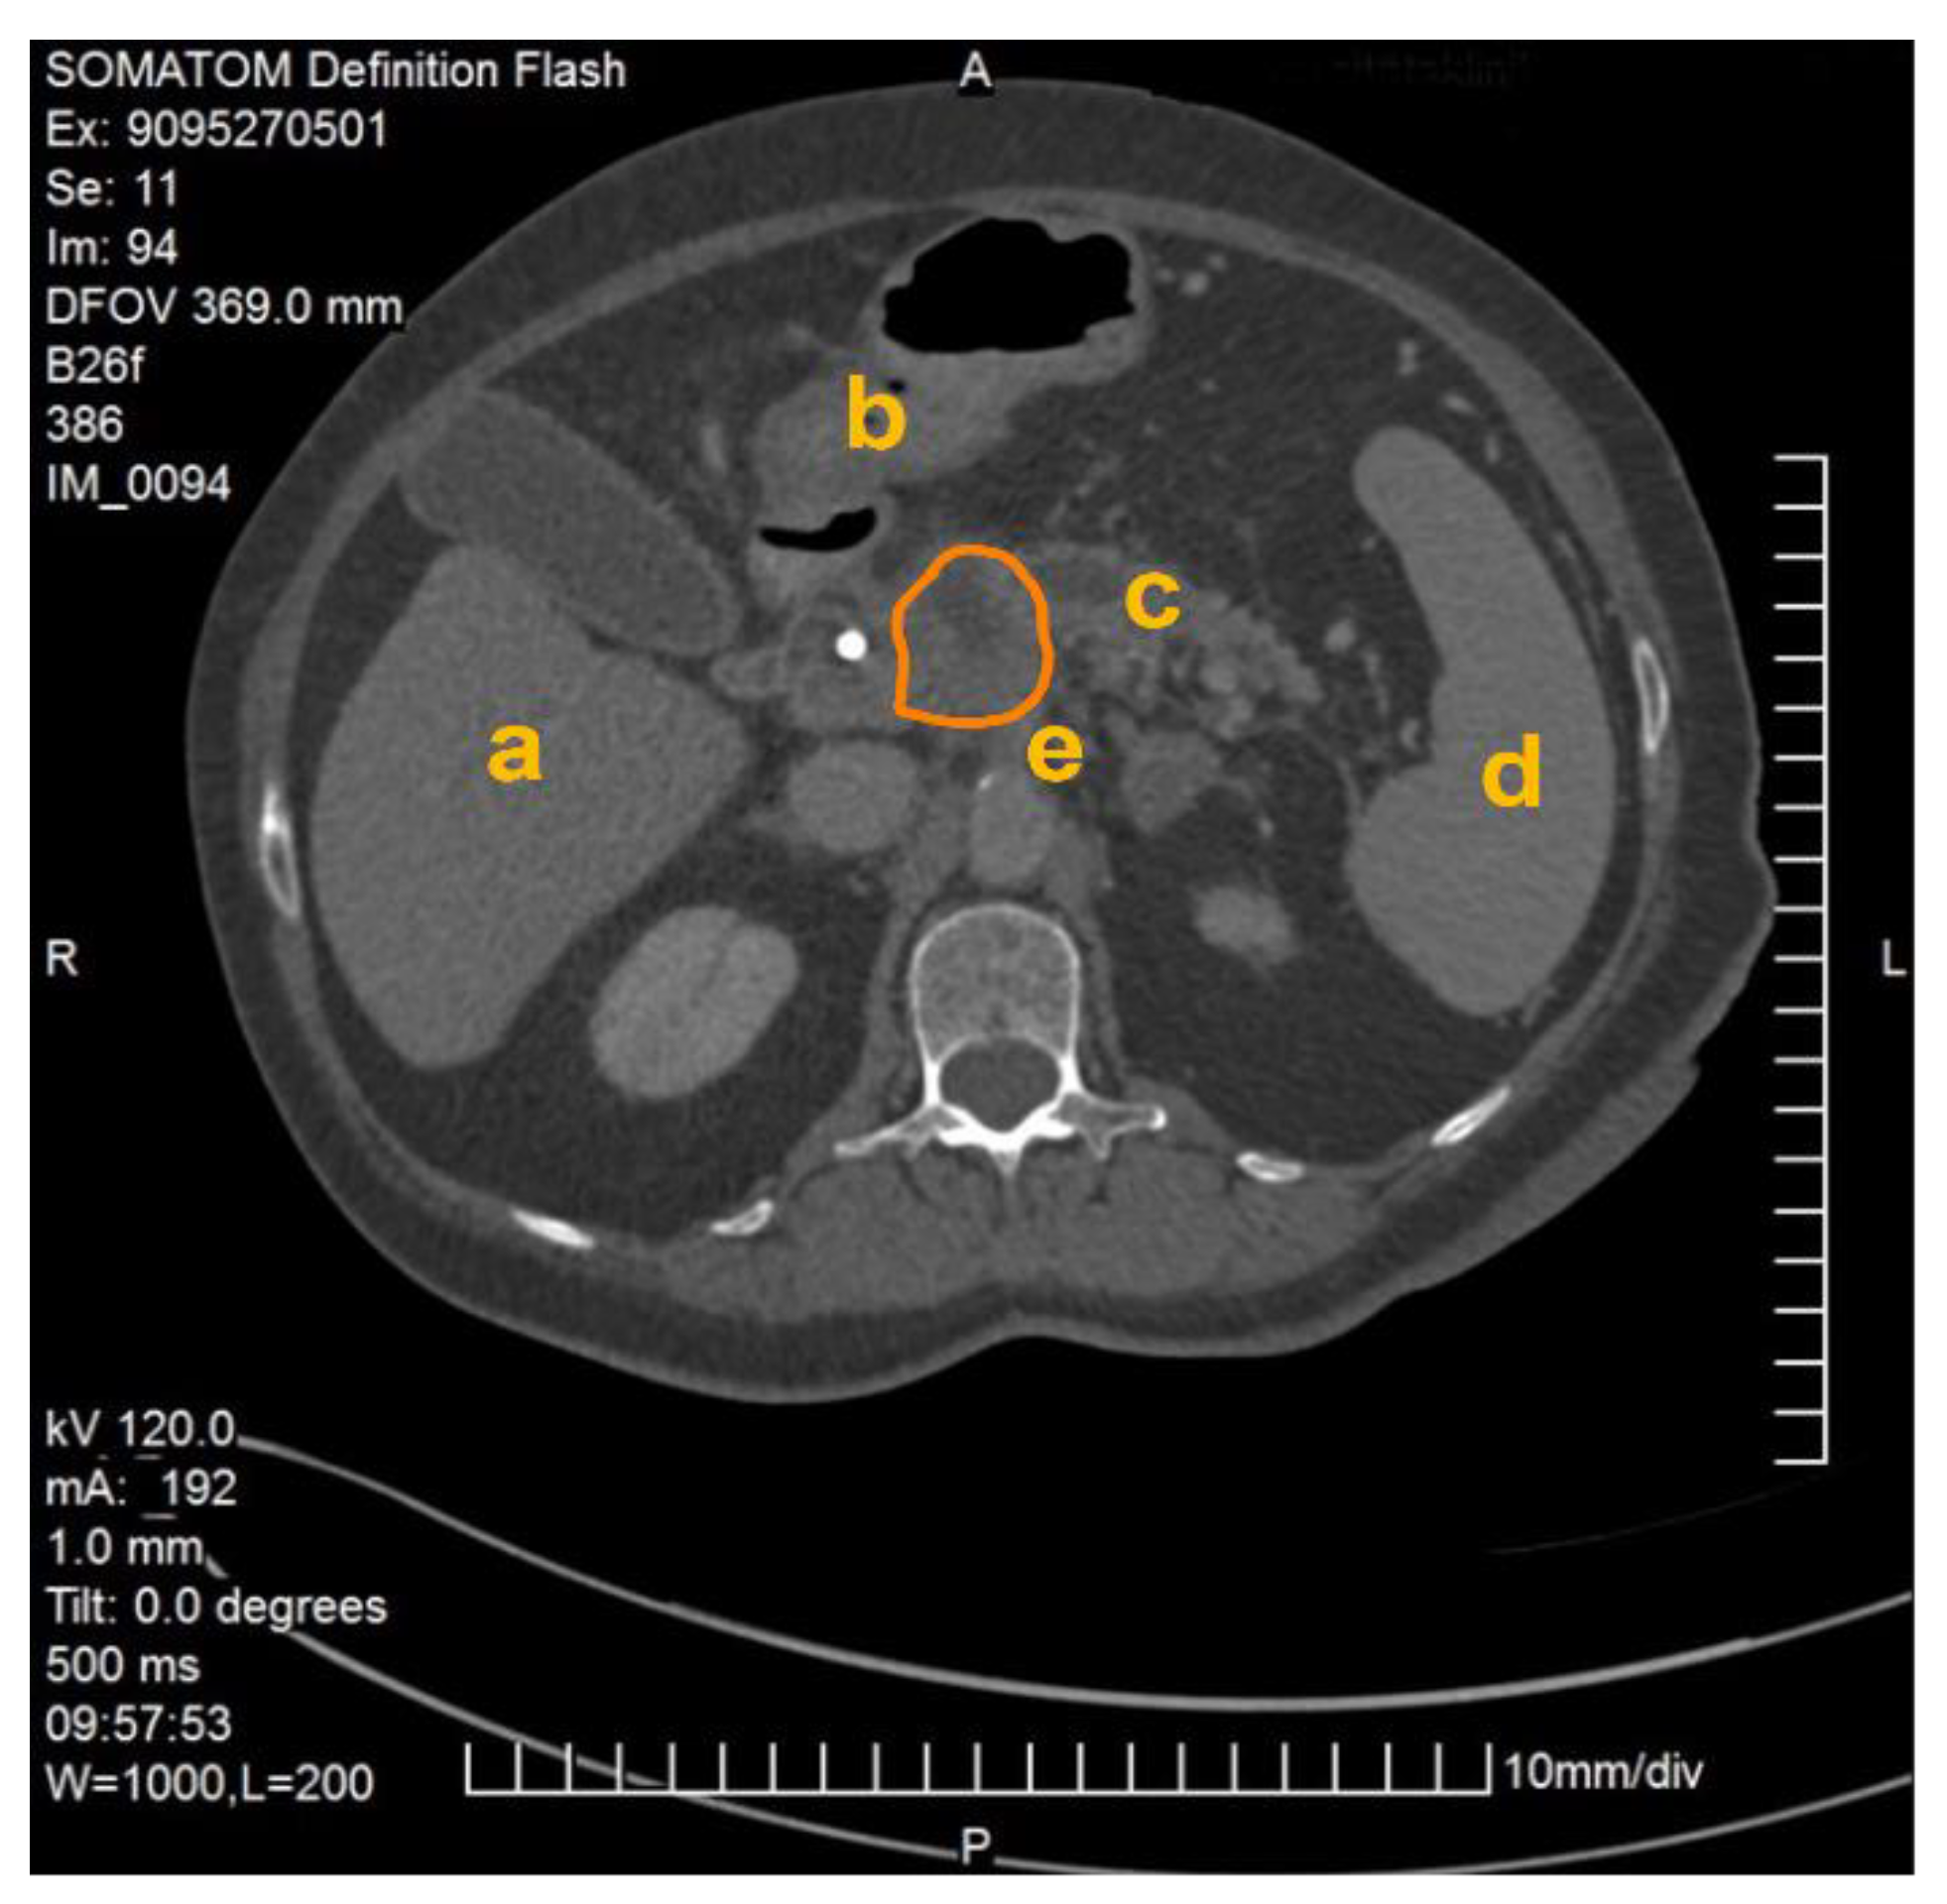

The method described was applied and validated on a patient with locally advanced PDAC. Figure 1 demonstrates one slide of the total CT scan. As this selected patient reported with jaundice, a splint was placed in the common bile duct. The images were exported as NIFTI files and anonymized (Step 1) before being further processed in the program ITK Snap (Step 2).

Figure 1.

CT scan of a patient with locally advanced pancreatic ductal adenocarcinoma. Visible are the pancreas with a splint in the head of the pancreas as well as the liver (a), the gastroduodenal junction (b), the dilated pancreatic duct (c), the spleen (d), the abdominal aorta and the origin of the coeliac trunc (e). The PDAC tumor is outlined in orange.